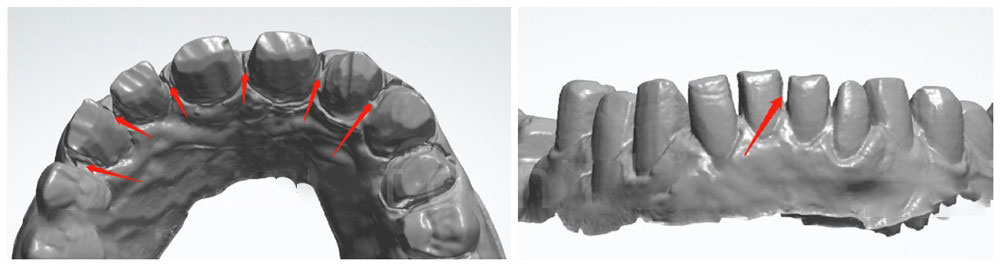

3. Leave enough space

Please prepare more teeth, so there is about 1.5mm space between teeth. We also need space for the occlusion (1.5mm). If doctors only prepare little teeth, there is no space for making details such as translucency and more color blending on the incisor. With a narrow space, dentists could have a hard time inserting crowns at the chairside.

Teeth preparation without enough space